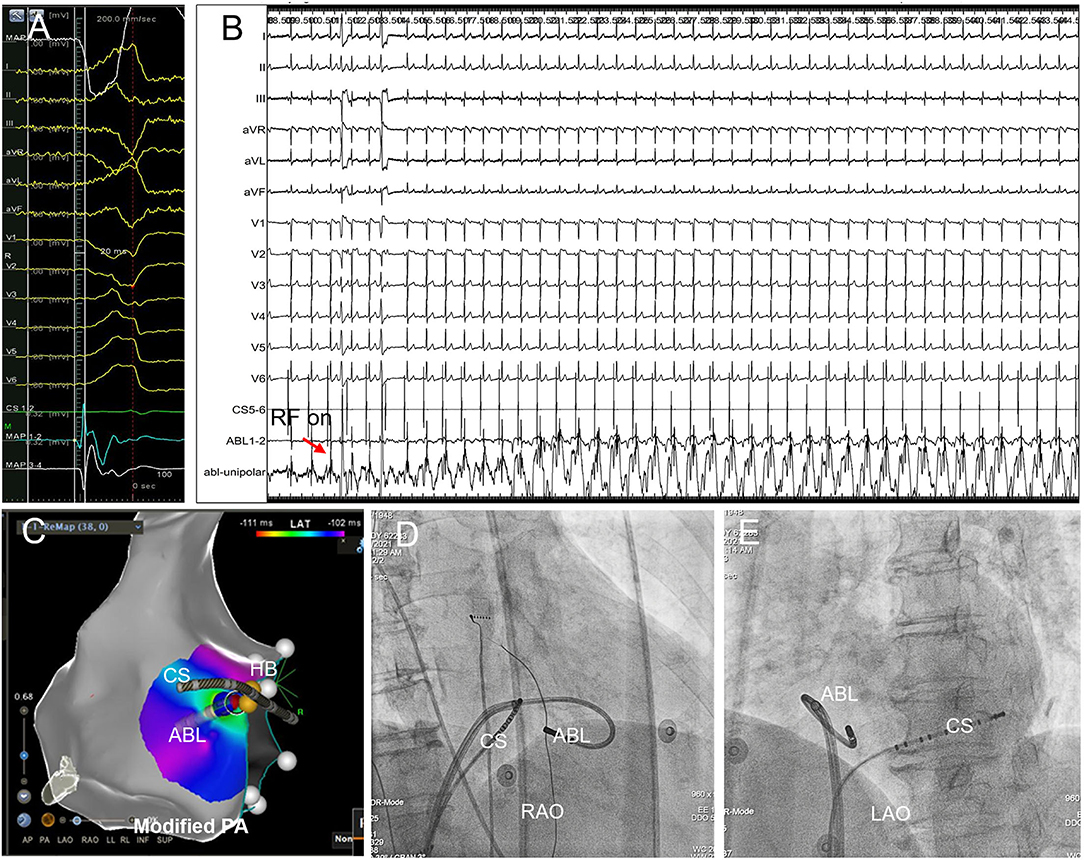

Figure 4. Successful B-SLTV ablation of right PHVA with the ablation target extremely close to the HB. (A) Tracings were unipolar MAP1, twelve-lead surface ECG, CS1−2, bipolar MAP1−2, MAP3−4. The local bipolar electrogram at the ablation target preceded the QRS onset by 20 ms with a sharp “QS” unipolar electrogram. (B) Saline-irrigated RF energy delivery 35W, 90s at this site successfully abolished the PVC, without junctional rhythm or AV conduction impairment. (C) The catheter tip was positioned beneath the SLTV ≈ 2 mm away from the HB. The blue dot represented the ablation lesion. (D,E) The B-SLTV placement of the ablation catheter was displayed on RAO and LAO projection. HB, the His bundle; CS, coronary sinus; ABL, the ablation catheter. PA, postero-anterior; RAO, right anterior oblique; LAO, left anterior oblique.

The earliest activation site was tagged on the geometry and served as the initial ablation target if it was >4 mm away from the HB, and if the HB-Right bundle branch (RBB) capture threshold by pacing at the earliest activation site was higher than that at the HB site (14). However, in case of the earliest activation <4 mm away from the HB, or if HB-RBB was captured with lower threshold at this site than the HB, attempt of ablation could be tried under close monitoring of junctional rhythm/AV conduction (Figure 4).

Right PHVA Ablation

RF ablation by the B-SLTV approach succeeded in 24 (66.7%) of 36 patients with right PHVA, and failed in the remaining 12 patients (Figure 5). The electrocardiographic and procedural data were compared between successful and unsuccessful B-SLTV ablation in Table 2. There was significant greater target -HB distance and lower prevalence of junctional beats in patients with successful B-SLTV ablation than in those without. ECG morphologies, the local ventricular activation preceding QRS onset (V-QRS), proportion of small HB potential at the target, average RF power, RF duration, number of RF delivery and fluoroscopy time were comparable between successful and unsuccessful B-SLTV ablation.

Among the electrocardiographic and procedural parameters, target-HB distance was the only factor that could predict successful B-SLTV ablation for right PHVA (OR 1.703; 95% CI 1.084–2.676, P = 0.02). ROC analysis showed target-HB distance cutoff value was 4.5 mm (sensitivity 66.7% and specificity 83.3%; Area under the curve = 0.773, 95% CI 0.614–0.931, P = 0.01). There was no significant difference in RF power and duration between cases with target-HB distance > 4.5 mm and those with target-HB distance ≤ 4.5 mm (35.0 ± 2.3 vs. 36.0 ± 3.4 W, P = 0.34; 155.5 ± 38.1 vs. 146.3 ± 34.2 s, P = 0.76, respectively).

Subsequent ablation in 12 patients with unsuccessful B-SLTV ablation was listed in detail in Supplementary Table 1. A-SLTV ablation successfully abolished the clinical VA in 6 of them. Totally procedural success was achieved in 30 (83.3%) of 36 patients with right PHVA. The remaining 6 patients experienced ablation failure even after thorough mapping and ablation at the neighboring structures (RVOT and three coronary cusps at the aortic root) and the left- parahisian region.